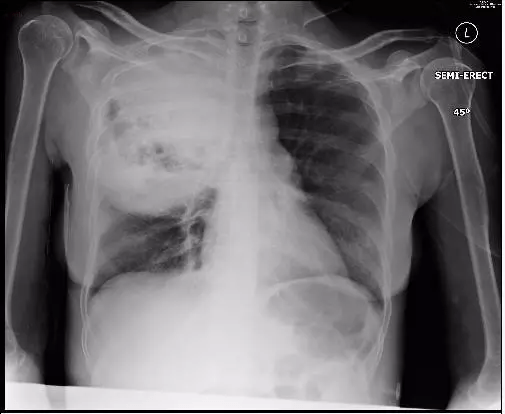

最后 , 再来回望一下 , 什么是叶间裂下坠 。

文章图片

图10-11